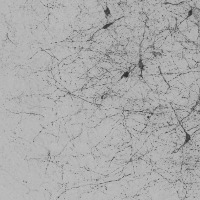

dopamine_th Computer Vision Project

The provided information seems to be insufficient to provide detailed use-cases. The model name, "dopamine_th" implies a possible connection to neurobiology, specifically, to dopamine neurotransmitters. Yet, the "th classes including th" part is unclear, as "th" is not a known term in either computer vision, biology, or bioinformatics domain. It might be a reference to certain classes in your data set, but without further context or clarification, it's challenging to provide accurate use cases. The image of a grey background also doesn't provide significant context. Could you please provide further details concerning this "th" term and more context related to the computer vision model?